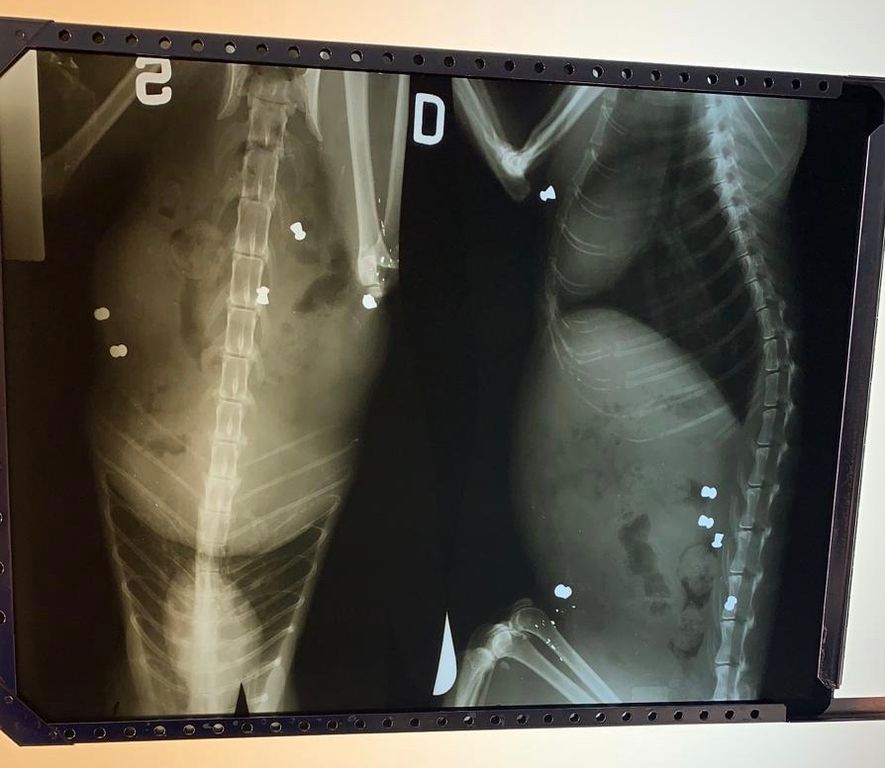

A Refrancore, in provincia di Asti, sparano ad un gatto con fucile ad aria compressa

La Lav sporge denuncia contro ignoti: "chi ha visto ci aiuti a trovare il colpevole"

Sparano ripetutamente con un fucile ad aria compressa a un gatto randagio e lo lasciano agonizzante. È accaduto a Refrancore, nell’Astigiano, vicino alla Casa di riposo.